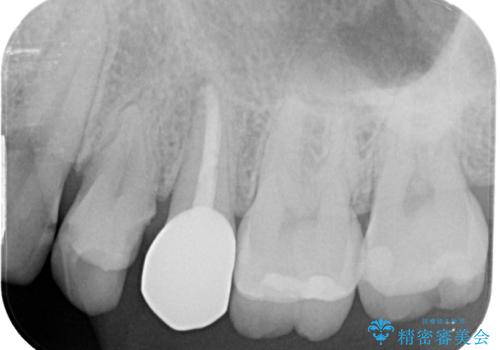

- 左上に違和感があるとのことで来院された患者様です。レントゲン撮影の結果左上の6番目の歯の近心側に虫歯を認め、フロスも引っかかる状態でしたのでセラミックインレーにて修復治療を行っていくこととしました。